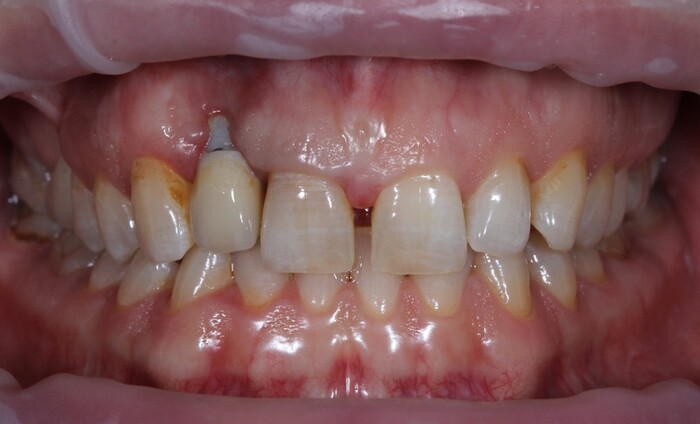

Но мне повезло, ко мне на прием пришла прекрасная девушка (а не усатый господин в плаще на голое тело) с ужасной, с ее слов, проблемой. Когда-то давно ей поставили имплантат в области верхнего бокового резца, но в связи с тем, что положение имплантата было неправильным, а одномоментно с имплантацией пластики десны не проводилось, последняя начала постепенно «подниматься», оголился абатмент (та часть, «за которую держится коронка»). Со слов пациентки, тем же доктором была предпринята попытка сделать пластику десны, не снимая этой коронки. Но, увы, развился некроз, что только усугубило ситуацию.

На момент моего осмотра это выглядело так:

Согласитесь, не особо эстетично. Ортопантомограмма: